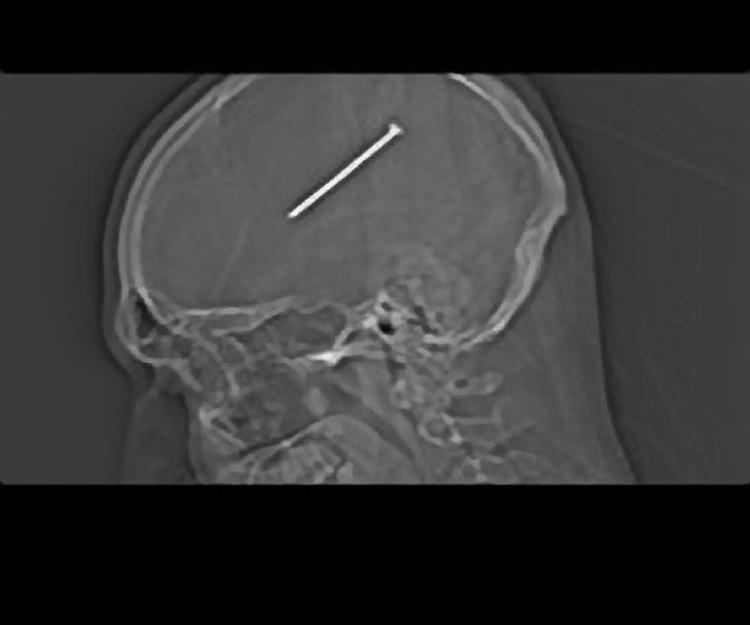

Det var en tirsdag aften ligesom så mange andre, da amerikaneren Dante Autullo forleden kom hjem fra sit arbejde i et værksted.

Han havde godt nok fået et sår i hovedet, mens han arbejdede, men ellers var alt fint. Han bad sin hustru Gail Glanzer om at rense såret, og så snakkede de ikke mere om det.